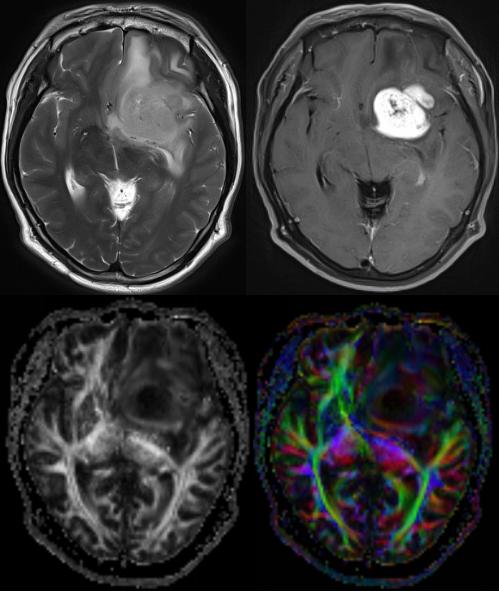

DTI显示不同年龄儿童胼胝体的纤维束发育情况